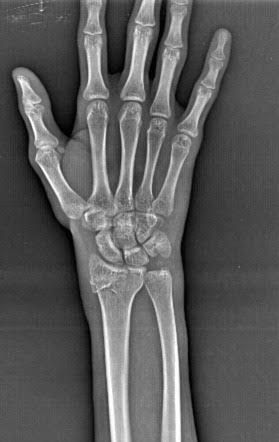

A Barton fracture is where you break part of your wrist and knock another part out of place. It usually happens when you fall on top of your bent wrist. The part of your wrist that breaks (your distal radius) is also part of your forearm. Your radius is the most commonly broken arm bone.